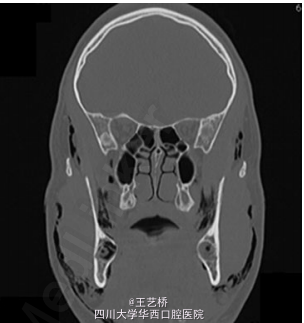

患者拔除双侧智齿后当天出现面部肿胀

检查发现患者整个面部肿胀,皮温正常,睁眼困难,轻度张口受限,轻度呼吸急促。触诊发现眶周、脸颊部、锁骨上窝有清脆捻发音。口内拔牙窝未愈合。

诊断:皮下气肿。患者住院进行预防性抗感染治疗,服用类固醇,同时为了避免软组织内气压过大,使用引流管控制气压